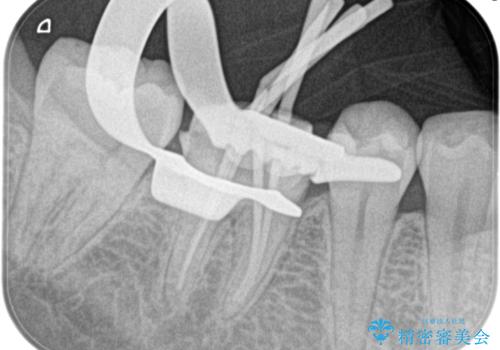

- 4日前から噛んだ時に痛むことを主訴に来院された患者様です。

歯髄壊死/症候性根尖性歯周炎の診断のもと、根管治療を行なっております。

根管治療は1回ごとにまとまった時間で治療を行うことにより2~3回の治療で完了します。

根管治療した歯は、クラウン修復が必要です。